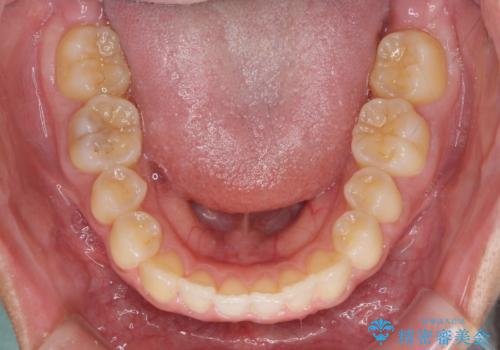

治療期間が世界的な感染症の流行時期と重なったため、海外と日本での往来が困難となり、治療継続が懸念されました。

それでも、しっかりとマウスピースを装着してくださったので、大きなトラブルもなく治療を終えることができました。